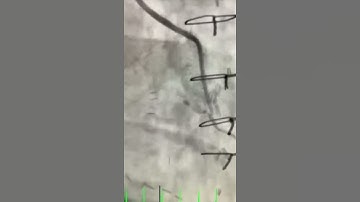

Gordon and Bypass